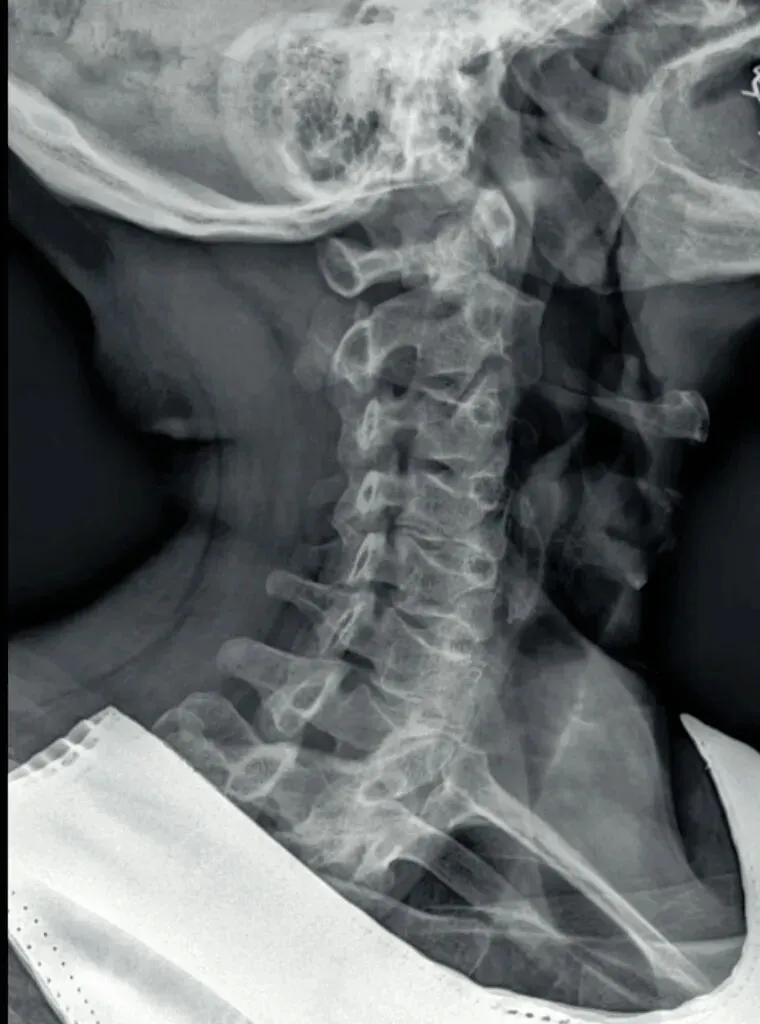

颈椎详细的X线解剖图谱参考:

一骨是是我们主要在颈椎侧位X线片中观察椎体的形态与结构,查看椎体是否规则,

椎体边缘有无变尖或呈唇样改变的骨质增生。

椎体骨质有无破坏,密度是否正常,如肿瘤或者感染。

椎体的高度是否均匀,有无压缩变形。椎体高度减小可能提示骨质疏松、压缩性骨折

或椎体的发育异常等。

二弓指的是颈椎生理曲度,在颈椎侧位X线片中,正常生理状态下呈现向前凸出的弧形曲线,呈半C型前凸类似弓形,是人体脊柱生理曲度的重要组成部分。颈椎曲度变化能够反映颈椎整体功能的变化。

常见的颈椎曲度改变有曲度变直和曲度反曲。